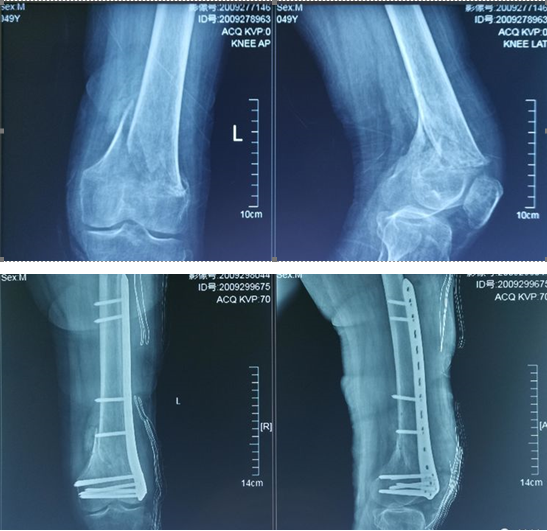

Версия XC Medico® с блокировкой дистального отдела бедренной кости предназначена для восстановления переломов, несращений и значительных причин, перипротезных сращений или остеоинтеграции, а также остеотомий дистального отдела бедренной кости. Коническая форма пластины делает возможной минимально инвазивную хирургию, эффективно уменьшая повреждение мягких тканей.

| Заявление: | фиксация перелома дистального отдела бедренной кости |